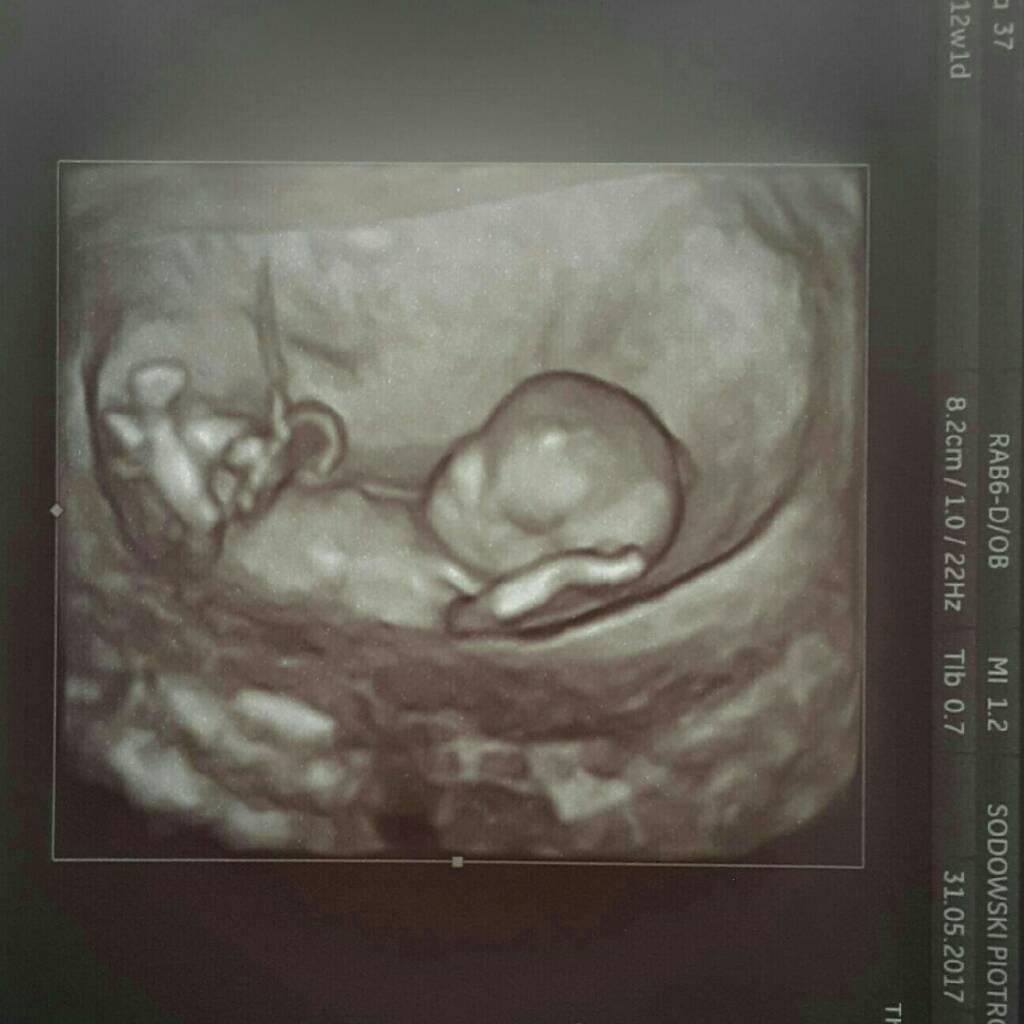

Dziewczyny unosze się nad ziemią. Wszystko ok . 7 cm małego człowieka.

Jestem taka szczęśliwa

1496251797-aaaaaa.jpeg

1496251805-aaaaaa.jpeg

Piękne zdjęcia :) i ten luz z ręką za głową no czad po prostu :)